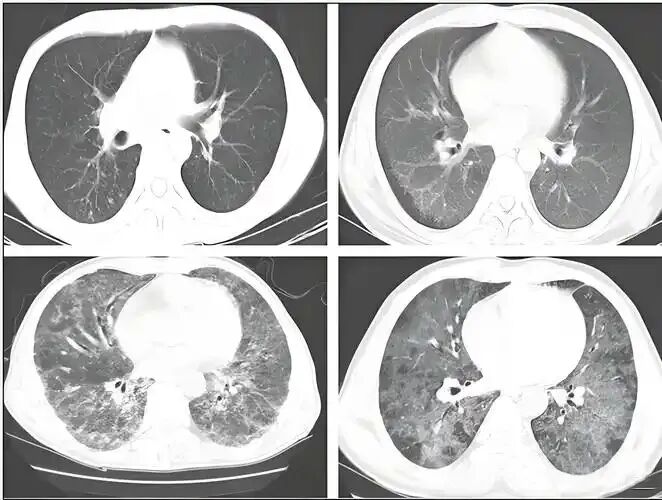

别忽视肺癌筛查

要是 50 岁以上、长期吸烟,或是有肺癌家族史,突然咳得声音变 “高调”(像金属音),甚至痰中带血,还莫名体重下降。

别拖!早去做肺癌筛查,早期发现干预,康复希望很大,不用谈 “癌” 色变。